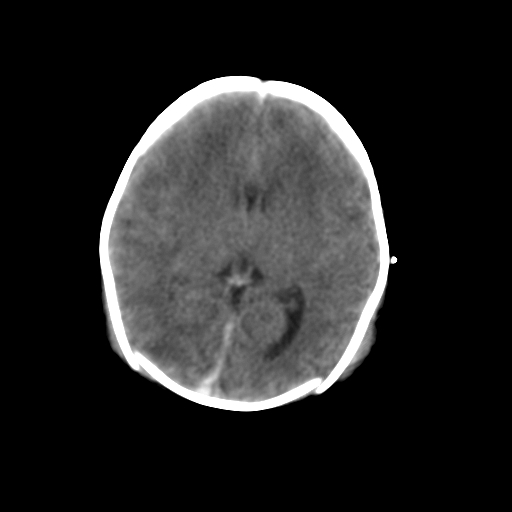

新生儿女2天,有窒息史,经抢救好转!白质最低ct值>23hu,请教各位老师:是否有出血?是否合并缺氧脑病?谢谢!

双侧额叶白质低,白质ct值低于18hu可以考虑水肿改变

后纵裂密度高,前纵裂密度低,比较来说应该考虑有蛛网膜下腔出血